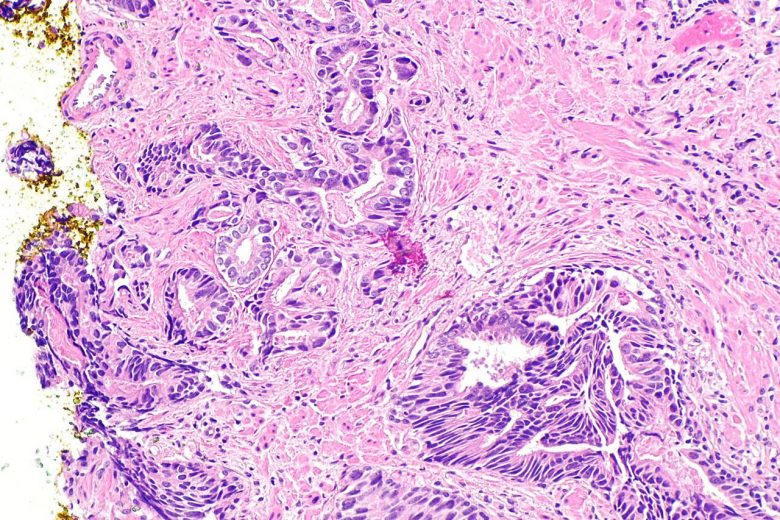

Gastric (stomach) cancer

“Gastric (stomach) cancer occurs when cancer cells form in the lining of the stomach. Risk factors include smoking, infection with H. pylori bacteria, and certain inherited conditions.

“Age, diet and stomach disease can affect the risk of developing gastric cancer. Symptoms of gastric cancer include indigestion and stomach discomfort or pain.

“Tests that examine the stomach and esophagus are used to detect (find) and diagnose gastric cancer.”